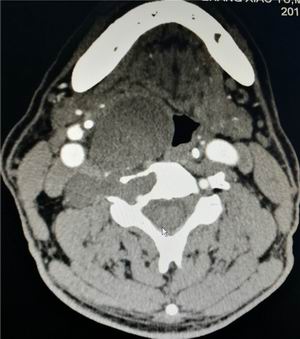

互联网医院在治疗大叶性肺炎同时,治疗组就病人病情进一步检查、讨论后,考虑患者颈椎肿瘤为神经源性良性肿瘤,位于环椎至颈5椎体水平右侧,颈3、颈4椎体及右侧横突孔破坏,呈分叶状。向外至颈内动脉后侧,咽喉部被挤压向左侧移位,肿瘤巨大,少见,周围解剖结构复杂;向左是咽喉要道,长时间压迫,壁薄,易损伤,术中、术后发生瘘道,继发感染,死亡率高;向右是颈内动静脉、迷走神经,后方是脊髓,稍有不慎脊髓损伤就瘫痪。上方是颌下腺、面动静脉,后上方有舌下神经,中间有甲状腺上动脉、喉上神经,后下方是甲状腺下静脉、喉返神经,后外侧有重要的椎动脉、静脉,神经、血管一旦损伤,很可能造成病人失血性休克、死亡、永久性神经损伤后遗症。可以说在一个狭小地区,布满地雷,而且下颌阻挡,安全操作空间非常有限。如此复杂病例,文献没有同样的成功案例借鉴,关键是病人目前除咽部异物感外,无明显其它症状,需要手术切除吗?手术能不能完成?手术后能不能不留后遗症?请北京、上海的大专家是不是成功率更高?

术前CT